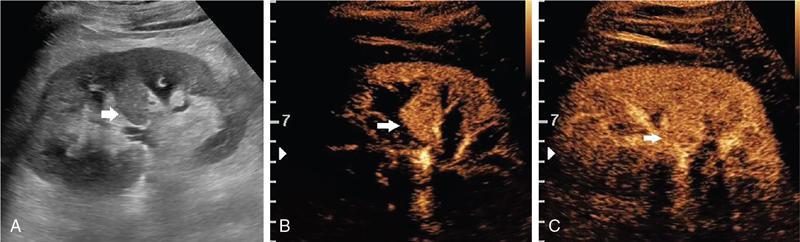

Drushi Patel CONTRAST-ENHANCED ULTRASOUND IN ADULT GENITOURINARY IMAGING Mridula Muthe Ultrasound is the initial screening examination for the evaluation of the renal morphology and suspected renal lesions due to its multiple advantages such as easy accessibility, bedside assessment, affordability and lack of radiation. Vascularity of the kidney and renal lesions can be studied with the use of colour Doppler ultrasound however, it provides information only about the macrovasculature. With the use of microbubble ultrasound contrast agents (UCAs) macro as well as the microvasculature can be studied. Contrast-enhanced ultrasonography (CEUS) is also more sensitive than Doppler ultrasound as it is not affected by blood velocity and angle of insonation of the ultrasound beam. In urology, the established applications of CEUS in adults include characterization of cystic lesions and differentiation between pseudotumours and solid lesions. Box 10.23.1.1 provides a list of European Federation of Societies for Ultrasound in Medicine and Biology (EFSUMB) recommended indications of CEUS in renal evaluation. EUROPEAN FEDERATION OF SOCIETIES FOR ULTRASOUND IN MEDICINE AND BIOLOGY (EFSUMB) RECOMMENDED INDICATIONS FOR USE OF UCA IN RENAL EVALUATION Renal ischaemia. Evaluation of solid renal lesions. Differentiation between solid renal lesions and pseudotumours. Characterization of complex cystic masses. Characterisation of indeterminate renal masses. Renal infections. Follow-up of nonsurgical complex masses. To improve lesion visualization in patients undergoing renal tumour ablation under US guidance and to detect residual tumour either immediately or after ablation. Isolated blunt moderate-energy renal trauma. Follow-up of trauma patients managed conservatively. Characterization of thrombus in renal vein and inferior vena cava. In patients with contraindications for CT- and MRI-based contrast media. Evaluation of lesions in transplant kidneys. Evaluation of ischaemia and vascular complications in transplant kidneys. Tumour response assessment to biologic therapy. Intracavitary CEUS for guiding percutaneous nephrostomy. Source: P.S. Sidhu, V. Cantisani, C.F. Dietrich, O.H. Gilja, A. Saftoiu, E. Bartels, et al., The EFSUMB guidelines and recommendations for the clinical practice of contrast-enhanced ultrasound (CEUS) in non-hepatic applications: update 2017 (long version). Ultraschall in der Medizin-Eur. J. Ultrasound 39 (02) (2018) e2–e44. CEUS involves the intravenous injection of UCAs consisting of gas microbubbles. These UCAs remain purely in the intravascular compartment as they are small enough to avoid filtration by the lungs and too large to enter the interstitial compartment. UCAs cause marked amplification of signals from the flowing blood, thus providing information about the microvasculature and parenchymal perfusion. Sonovue is a second-generation UCA and is the only UCA available in India. It consists of sulphur hexafluoride gas which is exhaled by the lungs and is surrounded by phospholipid monolayer which is metabolised by the liver, making it safe for patients with renal insufficiency. For renal evaluation, a dose of 1–1.5 mL of Sonovue is administered as a bolus dose followed by a 10 mL saline flush. CEUS is performed on machines with contrast-specific software’s using a low mechanical index (MI) technique. The use of a dual image display is beneficial for the evaluation of small lesions. A conventional B-mode ultrasound is first performed to acquire measurements, assess morphology and to detect focal lesions along with Doppler ultrasound to assess vasculature. However, due to limitations in the assessment of focal lesions, microvasculature, complex cysts, poor contrast between the lesion and cortex or medulla, it is preferable to perform a CEUS study for additional characterization. The enhancement pattern of the kidney is different than that of the liver due to the dual blood supply of the liver as opposed to afferent arterial supply and efferent venous drainage of the kidney. After an intravenous bolus of UCA, kidneys show intense enhancement. Contrast is first seen in the main renal artery, followed by its branches. CEUS has only two enhancement phases, that is cortical phase which lasts for 15–30 seconds and a parenchymal phase (enhancement of both cortex and medulla) for 25 seconds–4 minutes after UCA administration. The renal cortex enhances first, followed by the outer medulla which is followed by gradual enhancement of the pyramids (Fig. 10.23.1.1). During the washout phase first, there is a reduction in the medullary enhancement followed by a slower washout of the cortex. As kidneys don’t excrete UCAs, there is no opacification of the pelvicalyceal system. UCAs can act as a problem-solving tool in patients with renal failure as they are not nephrotoxic. Due to its excellent ability to depict renal vascularization, it can be used for detecting perfusion abnormalities. CEUS is useful for detecting vascular causes of renal function deterioration. Renal infarcts appear as wedge-shaped nonenhancing areas in all phases. Renal infarcts show a focal complete lack of parenchymal enhancement on CEUS whereas ischaemic areas show reduced enhancement. CEUS can confidently differentiate infarction from cortical necrosis by the demonstration of preserved hilar vascularity in the latter. Renal pseudotumours such as foetal lobulations, dromedary hump, parenchymal hypertrophy due to renal scarring and column of Bertini can be accurately differentiated from true tumours using CEUS. Pseudotumours show similar enhancement to the adjacent parenchyma and appear isoechoic on all phases while true tumours show different enhancement pattern on at least one phase (Fig. 10.23.1.2). True tumours will cause mass effect and distort the normal vascular architecture of the renal parenchyma whereas in pseudotumours the vascular architecture is preserved. In addition, the identification of medullary pyramids within the mass points towards it being a pseudotumour rather than a true mass. Cysts can be categorized according to the Bosniak classification using CEUS. Due to its superior spatial and temporal resolution, CEUS is considered superior to CT for detecting additional septations, wall or septal thickening and solid components (Figs 10.23.1.3–10.23.1.5). CEUS allows for real-time imaging of blood flow within the septae, wall or nodules within the cysts which may not be seen on CT or MR imaging. The sensitivity of CEUS is comparable to CT for the classification of renal cystic lesions as benign or malignant however, it is not as useful for staging. The follow-up of inoperable complex cystic lesions is better performed with CEUS rather than CT due to the absence of ionizing radiation. Complex cysts or masses with calcifications are not suitable for evaluation with CEUS. CEUS allows a detailed evaluation of the circulation in mass lesions as it demonstrates the macro as well as microvascular enhancement patterns. CEUS has more sensitivity than CT for detecting blood flow in hypovascular lesions. It can also be used to distinguish between complex cysts and solid lesions which remain equivocal on CT and ultrasound (B-mode and colour Doppler). CEUS is sensitive in identifying cystic areas, necrosis, debris and haemorrhage in small tumours that may be difficult to visualize on CECT and MR. Isoechoic lesions on conventional ultrasound are better characterized by CEUS (Fig. 10.23.1.6). Hyperdense renal lesions on noncontrast CT (NCCT) with HU values between 20 and 70 are better evaluated by CEUS which can classify these lesions as solid or cystic. CEUS can suggest the histological subtype of tumours. Clear cell carcinomas show heterogeneous hyperenhancement in the cortical phase and rapid washout along with a peripheral enhancing rim or pseudocapsule seen during the parenchymal phase. Papillary carcinoma shows progressive heterogeneous enhancement during the cortical phase and displays hypoenhancement as compared to the cortex on all phases. Malignant renal vein thrombus will show enhancement as compared to bland thrombus on CEUS. Tumours that are smaller than 3 cm commonly show homogeneous enhancement, regardless of their histologic subtype. Differentiation between angiomyolipoma, renal cell carcinoma and oncocytoma is not always possible. Although, CEUS has excellent sensitivity for the detection of malignancy, it has a higher false-positive rate as compared to CECT. Hence, combined use of CEUS for its high sensitivity and CECT for its high specificity may be performed for an accurate diagnosis. CEUS is effective in patients with complicated pyelonephritis, for identifying inflammatory parenchymal involvement, characterized by round or wedge-shaped hypovascular parenchymal areas, most conspicuous during the late parenchymal enhancement phase. An abscess is seen as a nonenhancing area, with or without peripheral or septal enhancement. CEUS can also be used for the follow-up of renal abscesses. All the aforementioned indications of CEUS in native kidneys also apply to renal transplants. Infarction, vascular complications such as arterial and venous thrombosis can be detected. Quantitative CEUS for assessment of graft dysfunction is a subject of active research. CEUS can be used as an alternative to CT especially in children with isolated blunt moderate energy injuries who are hemodynamically stable. It can also be used in the follow-up of conservatively managed trauma patients and in renal impairment. During Focused Assessment with Sonography for Trauma (FAST), the examination should begin with the kidneys as they have a fleeting enhancement. The kidneys are studied in the arterial phase with two separate doses administered for either kidney during FAST. On CEUS, lacerations, hematomas, and infarcts are seen as nonenhancing areas on late-phase images whereas contusions may show faint enhancement. Pseudoaneurysms and active bleeding are diagnosed on the arterial phase. Crucial complications such as devascularized parenchyma and acute cortical necrosis can also be diagnosed on CEUS. Pelvicalyceal system injury cannot be detected by CEUS as UCAs are not excreted by the kidneys. CEUS can be performed in conjunction with percutaneous ablation therapies. Preablation evaluation with CEUS is essential to assess lesion vascularity and to compare pre and postprocedure tumour viability. Also, the identification of a pseudocapsule predicts improved ablation efficacy. CEUS has demonstrated high sensitivity, specificity and accuracy for the early detection of residual unablated tumour. Dynamic contrast-enhanced ultrasound is a useful tool for early identification of responders and nonresponders, enabling tailoring of the treatment regimen. It is performed by two methods – Bolus injection of a UCA with time-intensity curve analysis (commonly used) and intravenous injection of UCA with disruption–replenishment analysis. In patients with chronic kidney disease, the contrast enhancement is less intense and fades earlier as compared to a normal kidney. CEUS aids in characterizing renal lesions in patients with renal failure. Characterization of lesions with indeterminate appearances in patients with renal dysfunction, on conventional US prevents unnecessary further evaluation with contrast-enhanced CT or MRI and further deterioration of the renal function as well as unwarranted investigations. CEUS nephrostomogram can be performed after percutaneous nephrostomography to confirm the correct positioning of its tip, detect the site of obstruction and to diagnose complications. UCAs can be safely administered in patients with minimal risk. They can be safely administered in patients with renal insufficiency as they are not excreted by the kidneys. Prior laboratory tests are not indicated as they are not nephrotoxic and don’t interact with thyroid function. Most adverse effects are mild such as nausea, headache, chest discomfort, chest pain and resolve spontaneously. The contraindications include known hypersensitivity, patients with right-to-left shunts, severe pulmonary arterial hypertension (pulmonary arterial pressure >90 mm Hg), uncontrolled systemic hypertension, and respiratory distress. The rate of anaphylactic reactions is significantly lower than iodinated contrast media and comparable to gadolinium-based contrast agents. Caution should be exercised in patients with severe acute coronary disease and in patients with unstable angina. CEUS is a rapidly evolving technique, can be conveniently performed as an extension of conventional ultrasound and acts as a valuable tool in the characterization of indeterminate renal lesions, especially when the lesion is small. The advantages of CEUS include quick assessment, real-time imaging, high contrast resolution, excellent safety profile, lack of ionizing radiation, great repeatability, and most importantly, ideal for contrast evaluation in patients with deranged renal function. DUAL-ENERGY AND SPECTRAL IMAGING IN GENITOURINARY SYSTEM Aditi Chaitanya Gujarathi-Saraf Dual-energy CT (DECT) also known as ‘spectral imaging’, was first conceptualized in the 1970s. However, the clinical applications of DECT have recently emerged as owing to improvements in postprocessing techniques. The development of a single-detector, single-source DECT (ssDECT) with the capability for rapid alternation between two peak voltage settings (‘fast switching’) and a dual-detector, dual-source DECT (dsDECT) system in last few years have made possible various applications in solving clinical problems. In DECT, the simultaneous use of two different X-ray beam energy settings (80 and 140 kVp) allows the differentiation of materials on the basis of their attenuation characteristics (material density). There are two major applications of DECT in genitourinary system. First being characterization of renal calculi to differentiate those containing uric acid (UA) from those which do not. The other application is to characterize small renal masses which include differentiating complex cysts from renal tumours, detection of solid growth in PCKD patients and detection of residual tumour after thermal ablation of a renal neoplasm. The principle of DECT imaging is based on the differential absorption of X-ray energy at variable kVp settings. In DECT, two energy levels (typically 80 and 140 kVp) are used to acquire images that can be processed to generate additional datasets. Thus, a tissue or any material in the body shows different degrees of attenuation when scanned at different X-ray energies. Conventional CT numbers (attenuation measurements in Hounsfield units) are related to the linear attenuation coefficient of a particular material. The unique linear attenuation coefficients obtained by imaging at two different energies can be used to discriminate between different materials (e.g. fat, calcium, iodine and water). The characterization of material on DECT depends on their CT number ratio (CTR) also called dual-energy ratio. DE RATIO = CT number of a given material in the low-energy image CT number of the same material in the high-energy image DECT and spectral CT can be performed by three techniques (Fig. 10.23.2.1): Two sets of material-specific images are created to detect the presence or absence of a material. The two basic materials selected should have significant difference in mass attenuation coefficients and atomic number. The two commonly selected pairs are: Iodine-specific images are most commonly used in the clinical practice. When iodine is paired with water, two separate image data sets are generated. On water density image, the voxels that show change in attenuation due to presence of iodine are removed. These are instead represented on iodine density images. Thus, virtual unenhanced images are generated which resemble the conventional unenhanced images. Renal calculus disease is a common disease affecting approximately 10%–14% of population in India commonly affecting 31–45-year-old patients. Accurate diagnosis of composition of renal calculi is crucial as the frequency of prevalence and recurrence rate of renal calculi is high in most states of India. The obstructing calculi can lead to obstructive uropathy, pyelonephritis, urinary sepsis with nearly 50% of the patients being affected by renal failure. There are multiple compositions of renal calculi, most common being calcium oxalate (70%), calcium phosphate (20%), uric acid (8%) and cystine (2%). In general, UA calculi have lower attenuation values than nonuric acid calculi (i.e. struvite, cystine and calcium) on conventional CT. However, it may be difficult to distinguish between the two due to overlap in attenuation values. Here DECT becomes a problem-solving tool as it uses the two-material differentiation approach. Thus, in addition to size and location, DECT provides information about the composition of calculi to the urologist. DECT has high sensitivity of 88%–100% and high accuracy of 93%–100% to differentiate UA calculi from nonuric acid UA calculi. This is of utmost clinical importance as UA calculi can be treated medically whereas non-UA calculi require invasive methods of treatment such as extracorporeal shockwave lithotripsy (ESWL) or percutaneous nephrolithotripsy (PCNL). In clinical practice, NCCT scan of KUB region is performed at 80 and 140 kVp to generate two image datasets and obtain the DE ratio. A cut-off value of DE ratio of 1.2 is used to differentiate UA calculi from non-UA calculi (Fig. 10.23.2.2). Following flow chart shows differentiation of renal calculi based on DE ratio.